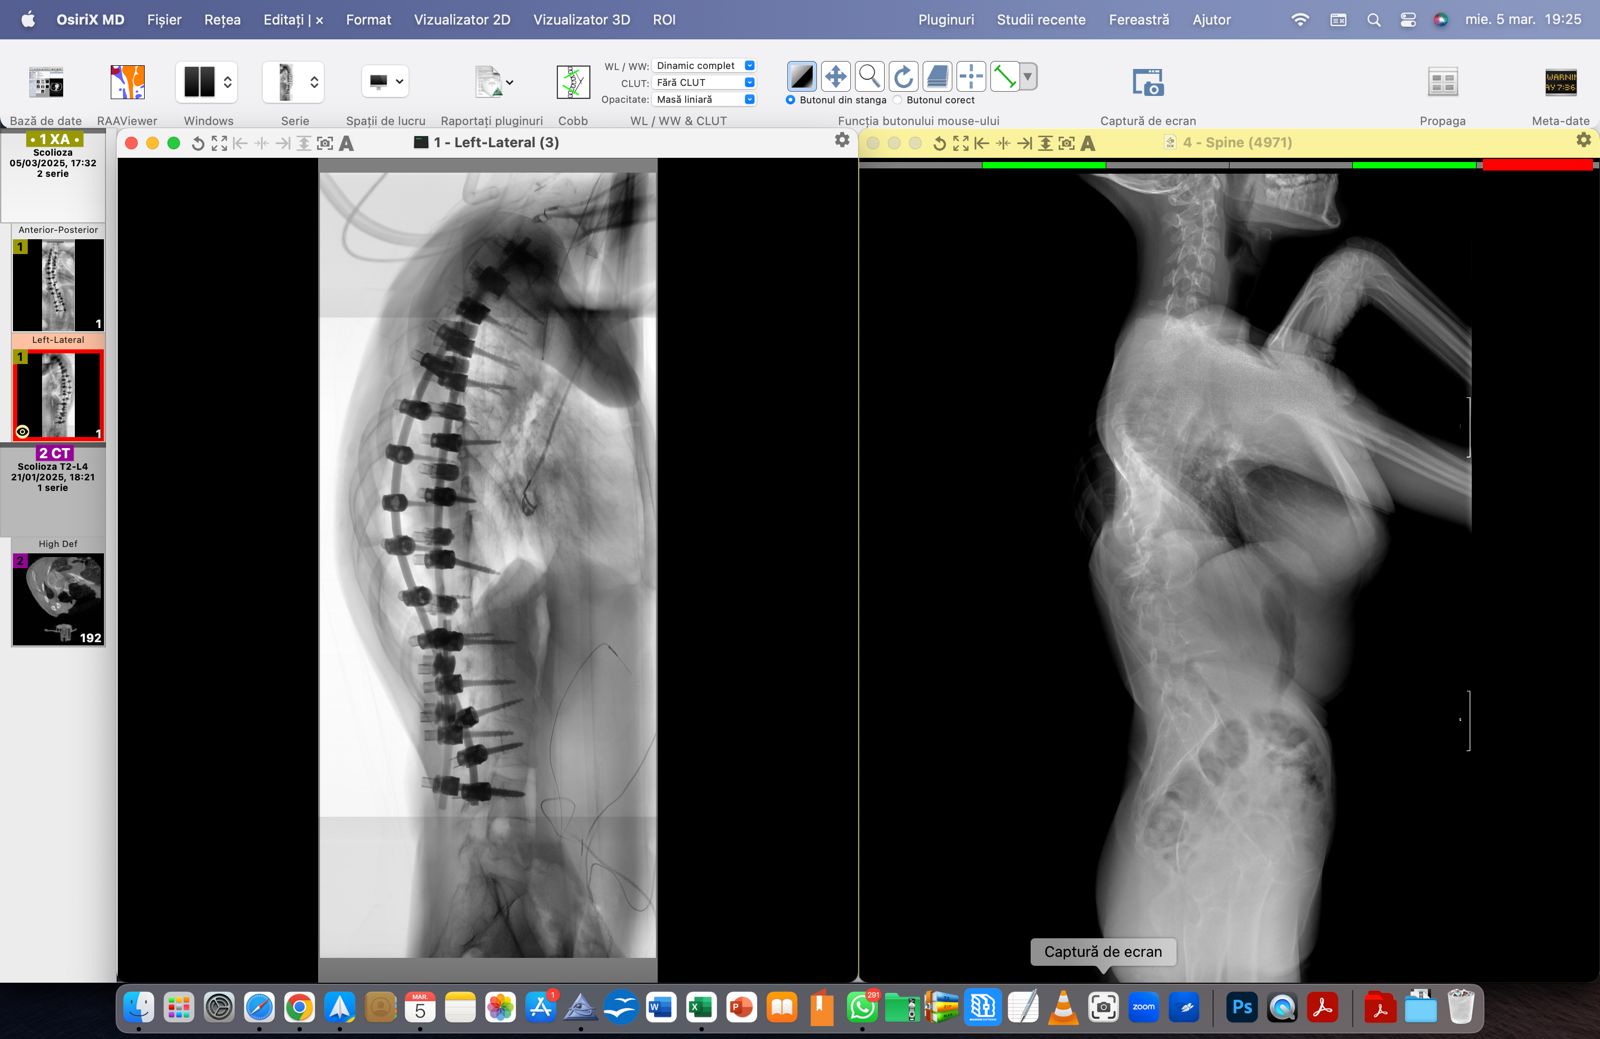

Denisa – o luptătoare de doar 15 ani – se întoarce acasă! Cu inima plină de recunoștință și cu speranță în suflet. După două intervenții dificile, un unghi Cobb de 143° a devenit 57°! O diferență uriașă care înseamnă nu doar o coloană mai dreaptă, ci o viață nouă, o șansă reală la normalitate.